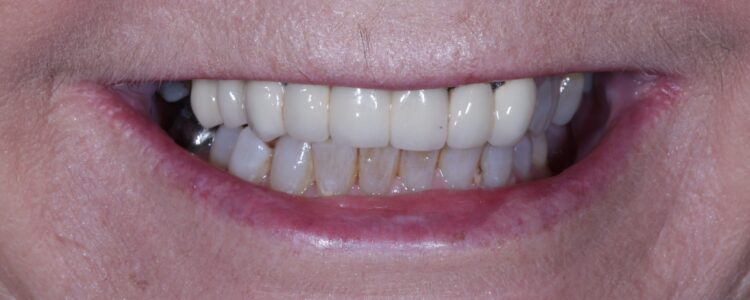

The patient returned to the practice for review two weeks post-surgery and to confirm successful and otherwise uneventful healing. Discomfort was minimal and she reported being very satisfied with the outcome. After a healing period of three months, the patient returned to begin making the final prosthesis. Good soft tissue adaptation was noted around the temporary prosthesis and the buccal contour was successfully maintained.

Upon professional reflection, this case went according to plan, emphasising the importance of meticulous assessment and preparation prior to implant surgery. The guided approach helped to ensure the precise positioning of the implants which facilitated connecting the temporary bridge. This, alongside the implant selection, was crucial for maximising on the limited bone available for primary stability.

The Tapered Pro Conical implant from BioHorizons Camlog is a game-changer, offering a new narrow diameter option for enhanced versatility in areas with limited bone. Its conical connection improves the implant-prosthetic interface and emergence profile, delivering optimal aesthetics, while the titanium alloy (Ti-6AL-4V ELI) delivers exceptional strength. It is indicated for use in the mandible and maxilla, single tooth replacements, fixed bridgework, and overdentures. With high insertion torque limits of up to 136 Ncm, the Tapered Pro Conical implant also ensures stability and success in a range of clinical scenarios.